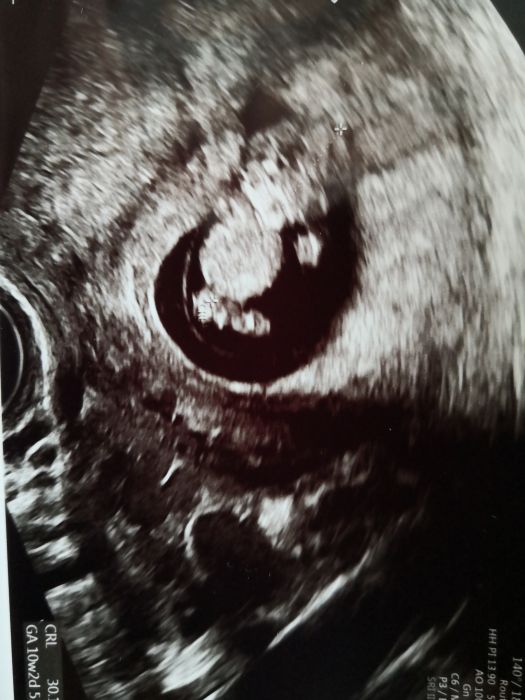

Tak dnesni kontrola za mnou. Jsem docela rada. Tlak opet nahore. Utrogestan mam brat dal, nicemu to neuskodi ale vse vypada dobre. A moc se uvidi zitra. Minule tam byl extremni vyskyt bakterii, proto ta antibiotika. Mela trochu strach kvuli tomu krvaceni, aby se to nedostalo nekam kam nema. No nicmene, dnes v moci opet bakterie. Ale pockaji do zitra, zda to neni ovlivneno tim utrogestanem. Ktery kdyz se vylucuje z tela, tak i s vytokem a ten castecne nejake bakterie obsahuje prirozene take, takze to mohlo ovlivnit vysledek. Pred odebranim moci, je potreba se poradbe otrit a nechat trochu moc odtect a pak az nabrat. Ale ja vzdycky kdyz tam jdu mam problem jim do toho kelimku vubec neco vypustit, tak jsem rada za kazdou kapku. Jinak mimco se ma velmi dobre i nam zamavalo. Videli jsme opravdu vse krasne. I prstiky jsme mu mohli spocitat. A meri krasnych 30mm.Pridavam obrazek. A budu verit, ze zitra jen zavolaji ze dalsi antibiotika netreba. Jinak se me ptala, jak mi po nich bylo, ze jsou pratelske k mimcu, ale velmi nepratelske k traveni a zaludku. Tak jsem popravde rekla, ze to byl mazec.

Krásná fotka Tery